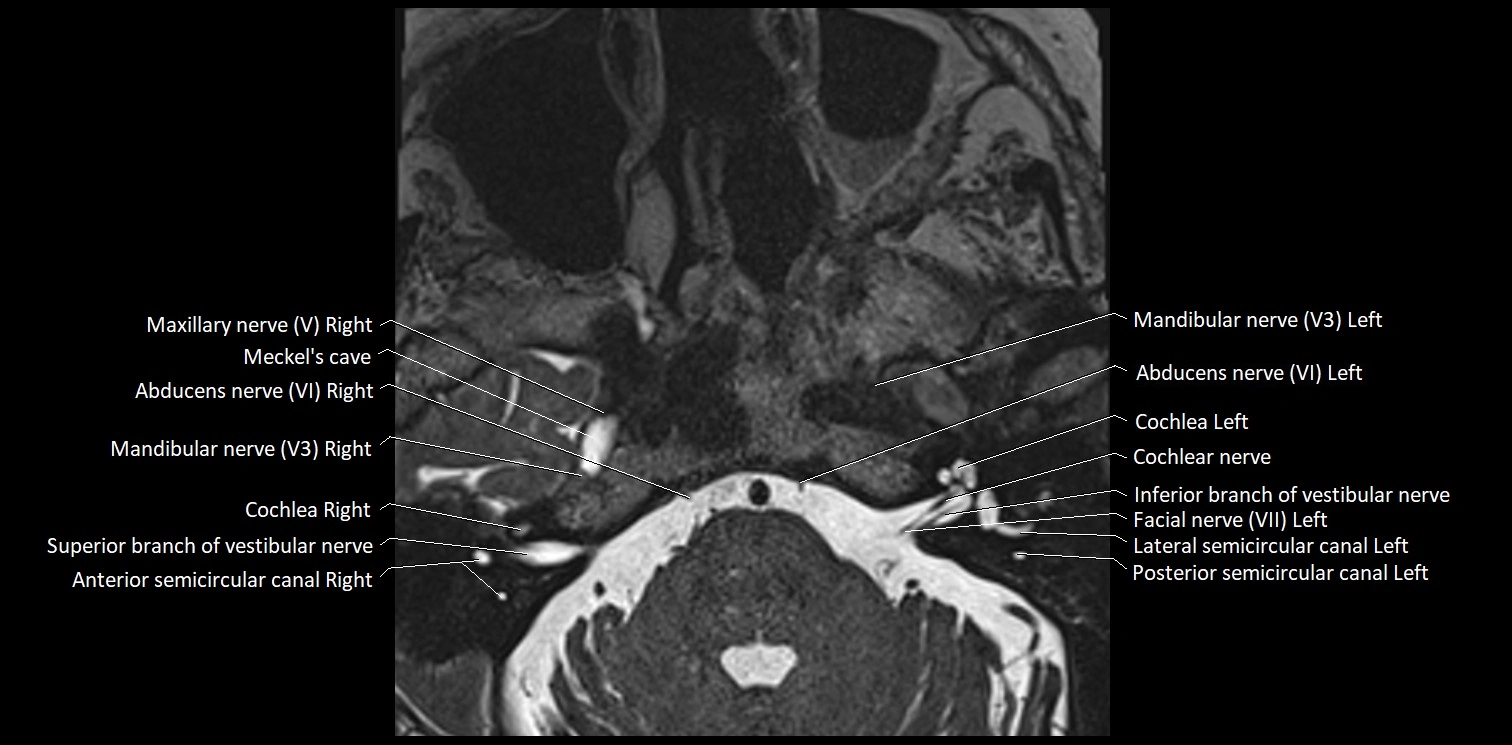

MRI Appearance

• The abducens nerve is a small, thin, linear structure

• Best visualized on high-resolution T2-weighted 3D MRI sequences (e.g., FIESTA or CISS)

• Seen as a hypointense (dark) line running from the brainstem at the pontomedullary junction, traversing the prepontine cistern, and entering Dorello’s canal under the petrosphenoidal ligament, then into the cavernous sinus, and finally the orbit

• May be challenging to visualize in standard MRI due to its small size

• Pathology may be inferred by absence, displacement, or enhancement of the nerve

MRI images

image